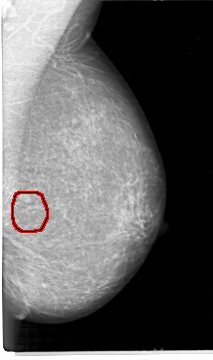

D_4026_1.LEFT_CC

LEFT_CC LINES 5386 PIXELS_PER_LINE 3106 BITS_PER_PIXEL 12 RESOLUTION 43.5 OVERLAY

FILE: D_4026_1.LEFT_CC.OVERLAY

TOTAL_ABNORMALITIES 1

ABNORMALITY 1

LESION_TYPE MASS SHAPE OVAL MARGINS OBSCURED

ASSESSMENT 0

SUBTLETY 3

PATHOLOGY BENIGN

TOTAL_OUTLINES 1

BOUNDARY